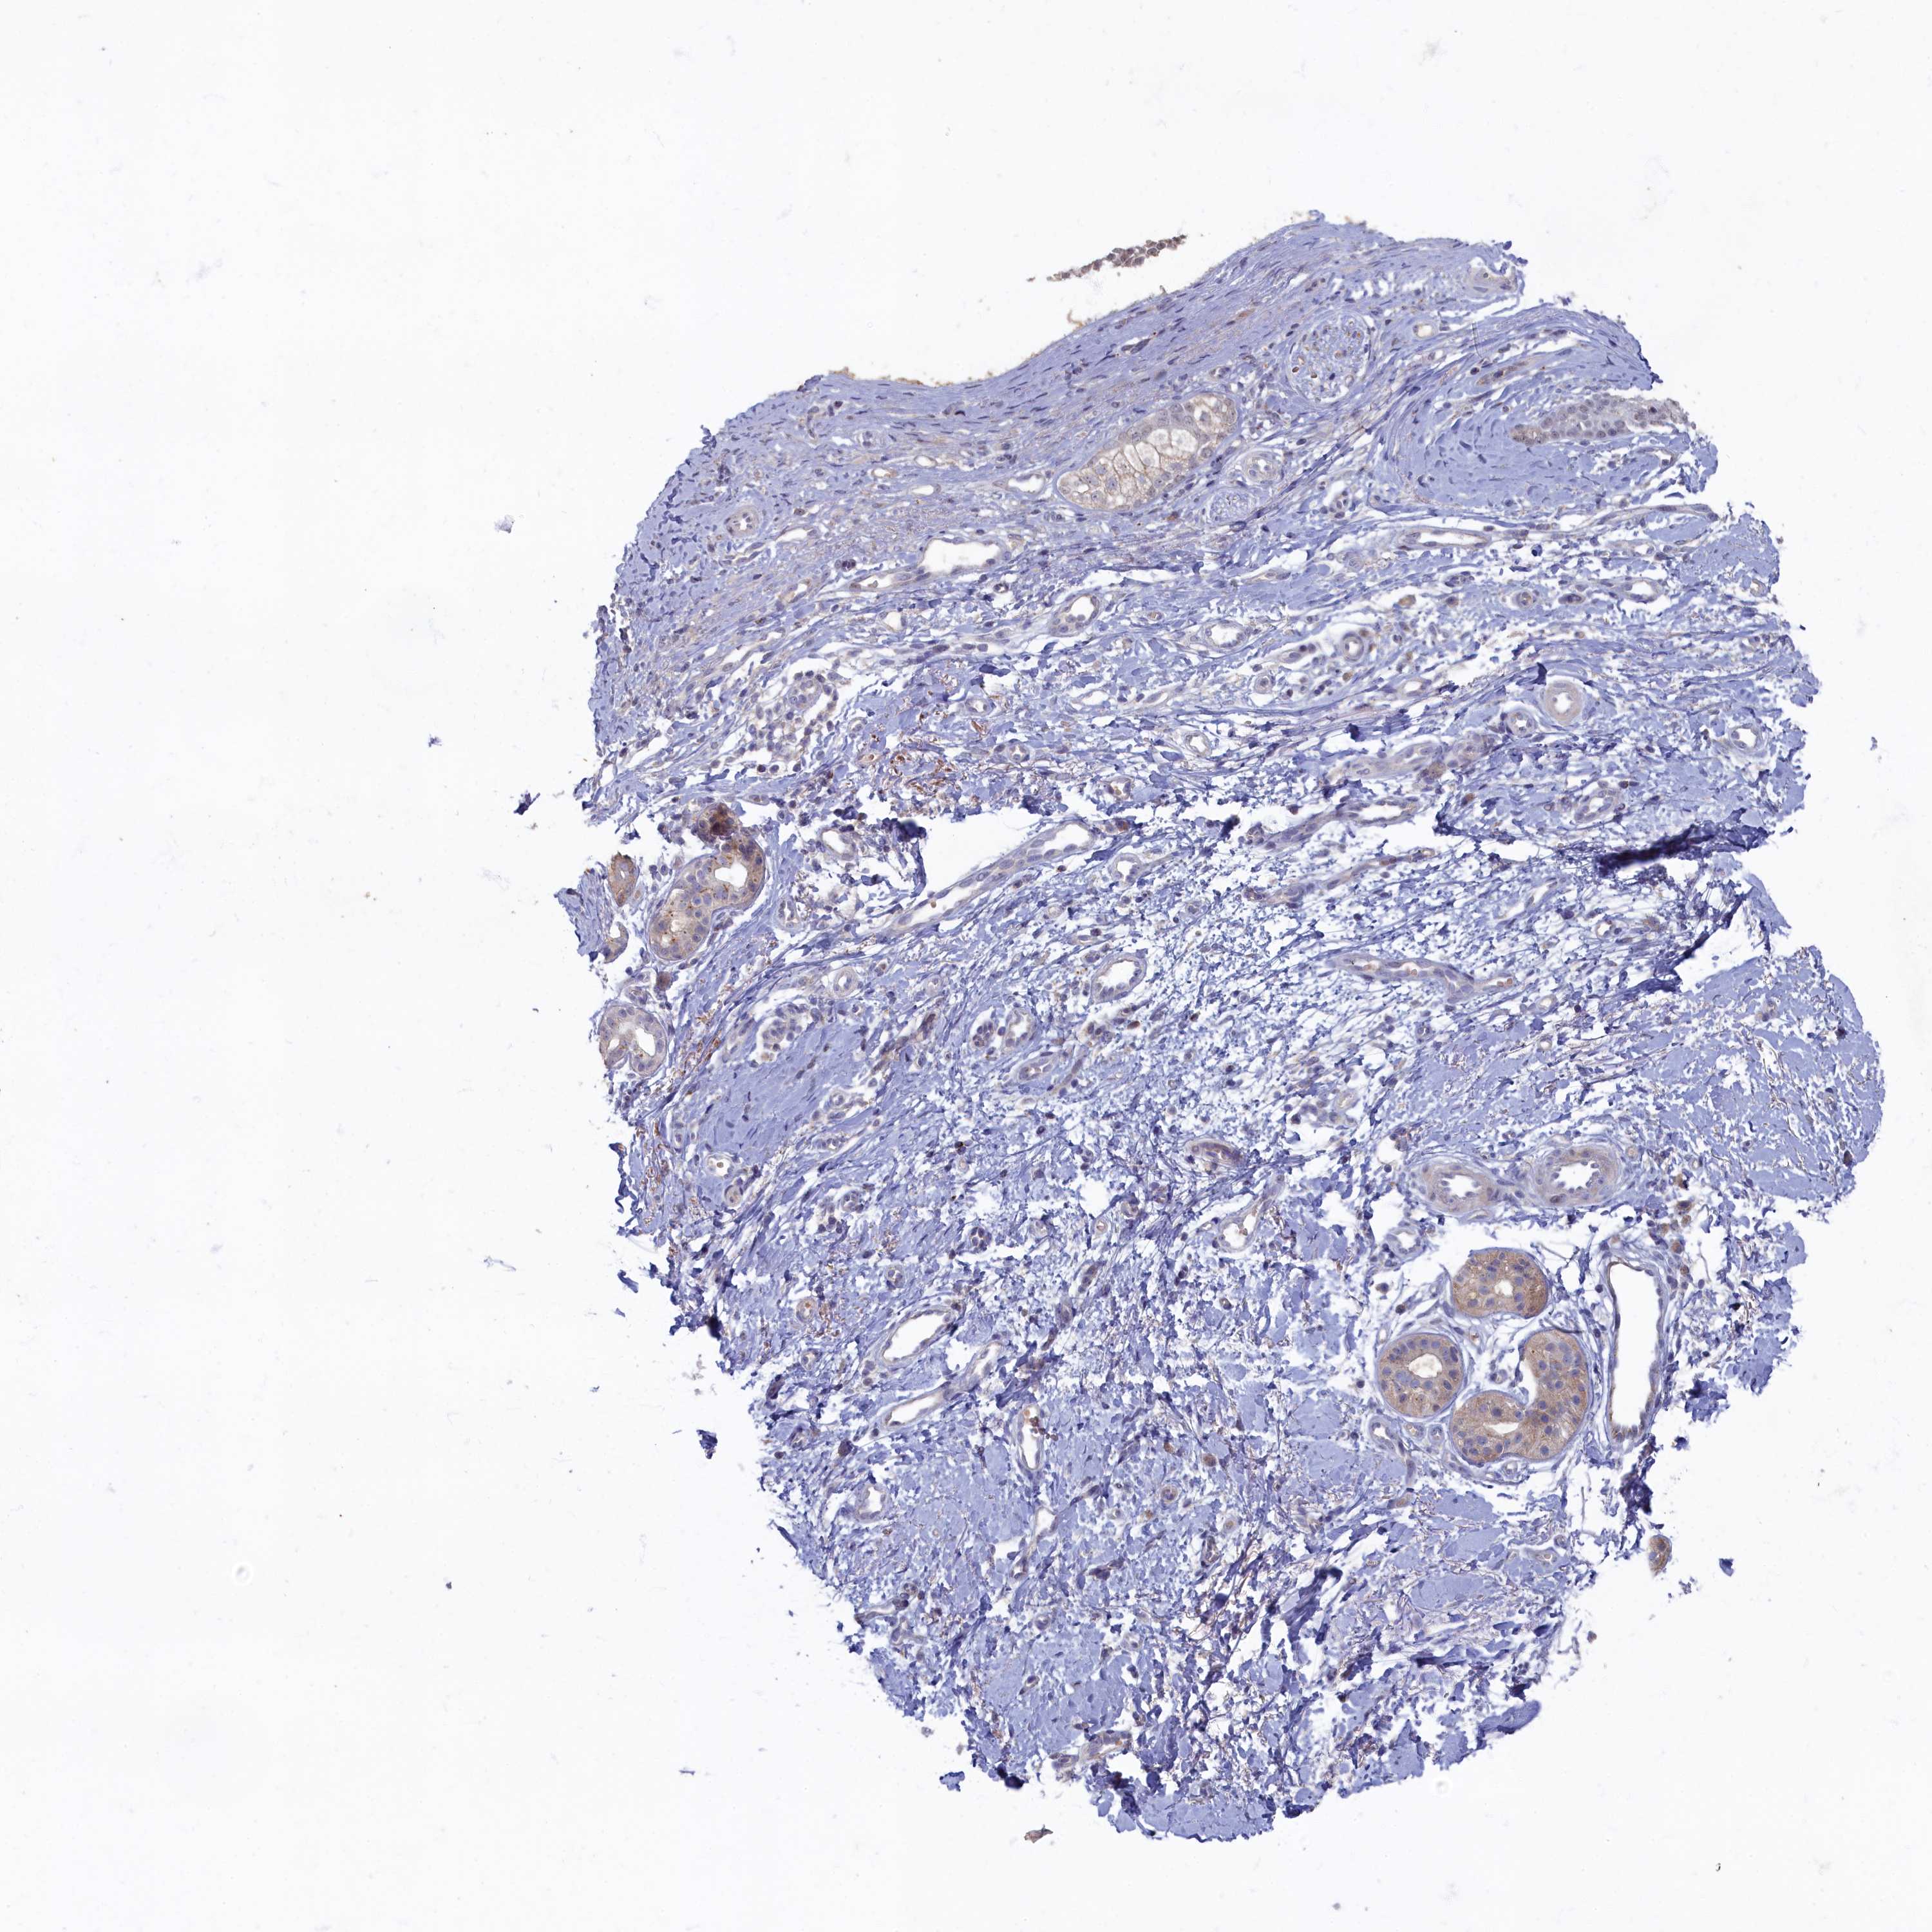

SKIN CANCER - Protein expressioni

A mouse-over function shows sample information and annotation data. Click on an image to view it in a full screen mode. Samples can be filtered based on level of antibody staining by selecting one or several of the following categories: high, medium, low and not detected. The assay and annotation is described here.

Antibody stainingi

Antibody staining in the annotated cell types in the current human tissue is reported as not detected, low, medium, or high, based on conventional immunohistochemistry profiling in selected tissues. This score is based on the combination of the staining intensity and fraction of stained cells.

Each image is clickable and will lead to virtual microscopy that enables deeper exploration of all samples and also displays staining intensity scores, fraction scores and subcellular localization as well as patient and tissue information for each sample.

Antibody HPA027295

Antibody HPA027372

Staining

High

Medium

Low

Not detected

Intensity

Strong

Moderate

Weak

Negative

Quantity

>75%

75%-25%

<25%

None

Location

Nuclear

Cytoplasmic/membranous

Cytoplasmic/membranous,nuclear

Basal cell carcinoma

Squamous cell carcinoma, NOS

Squamous cell carcinoma, metastatic, NOS